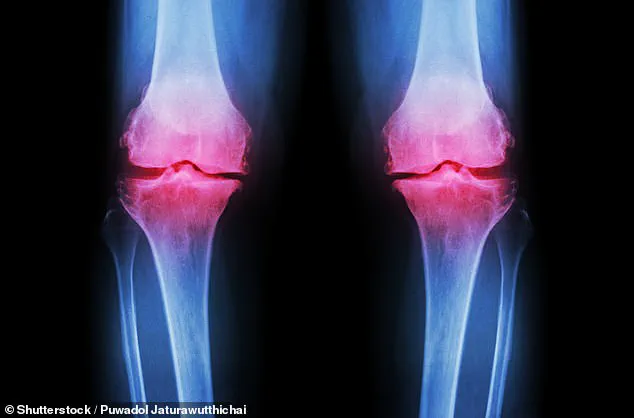

Osteoarthritis is a condition of gradual decay.

It occurs when the protective cartilage at the ends of bones wears away over time, leading to painful friction between bones as they rub against each other.

This process, often exacerbated by age, obesity, or previous joint injuries, results in swelling, stiffness, and a progressive loss of mobility.